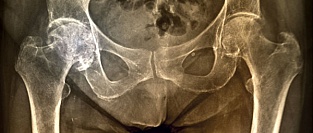

Сравнительная эффективность НПВС при остеоартрите. Результаты мета-анализа

Диклофенак в дозе 150 мг/сутки оказался наиболее эффективным нестероидным противовоспалительным препаратом (НПВП, НПВС) и с точки зрения обезболивающего действия, и с точки зрения улучшения функции сустава при остеоартрите (ОА) коленного или тазобедренного сустава.

В мета-анализ включались РКИ с участием пациентов с ОА тазобедренного или коленного суставов, в которых в каждую из групп лечения были рандомизированы не менее 100 пациентов. В список изучавшихся препаратов вошли ацетаминофен, рофекоксиб, лумиракоксиб , эторикоксиб, диклофенак, целекоксиб, напроксен и ибупрофен.